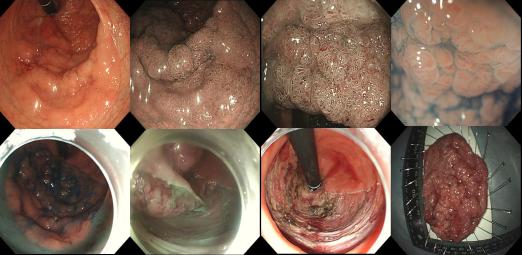

消化内科编制床位141张,年门诊平均就诊量约十万余人次,出院约6000余人次,内镜诊疗60000余人次,手术或治疗4千余例。我院地处川东北地区,长期收治不明原因腹水、不明原因消化道出血、不明原因腹痛、急性重症胰腺炎、肝硬化伴严重并发症及消化道大出血等疑难危急重症病人。作为川东北地区消化系统内科治疗的标杆,消化内科一直致力于示范和推广高水准的消化道诊疗技术,为提高诊疗技术,为广大患者提供更好的服务,我科购进了奥林巴斯小探头超声内镜、纵轴线阵扫描超声胃镜、奥林巴斯290色素放大内镜(NBI)、十二指肠镜、富士7000放大内镜、富士双气囊小肠镜等内镜下诊疗的高端设备。消化内科极其重视消化道肿瘤的早诊早治及消化内镜下一系列医疗技术,开展了EMR、 ESD、STER、POEM、EUS及内镜下止血等手术。同时,还大力开展消化放射介入治疗如ERCP等多项介入技术。消化内科联合急诊医学科、介入科、普外科等多科建立危险性消化道出血 MDT 团队,建立“危险性上消化道出血救治区域中心”,7×24 小时绿色通道,提供全面、优质诊疗方案,缩短危险性消化道出血急诊救治时间,大大提高了患者生存率。在临床工作中努力深化亚专科和各专业组建设,各专业组通过进修学习及各类学术交流、病例研讨等活动,不断提升团队整体实力,为患者提供更精准、更专业的医疗服务,努力在医学亚专业领域内实现新的突破与飞跃。

ERCP

Spyglass

POEM治疗贲门失弛缓症

内痔内镜下微创治疗

ERAT治疗阑尾炎

食管胃底静脉曲张套扎、硬化术